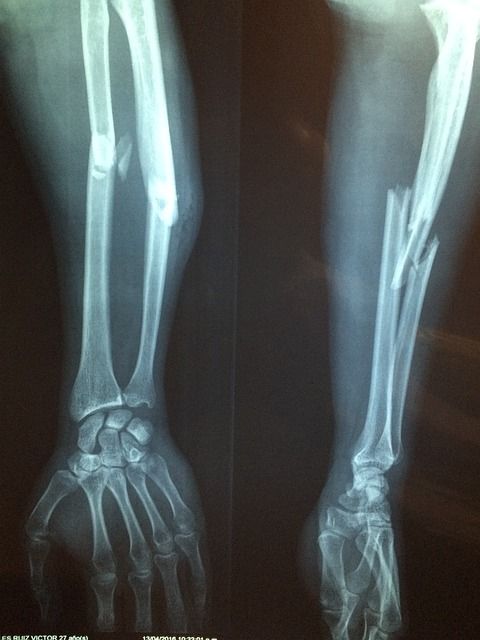

그 외에도 혈액 검사로 요산 농도를 측정하고, X선이나 초음파, CT 등의 영상 검사로 관절 손상과 통풍 결절을 확인할 수 있습니다. 급성 발작 시 혈중 요산 농도가 일시적으로 떨어질 수 있으니, 증상이 없을 때 검사를 반복하는 경우도 있습니다.

| 영상 검사 | X선, 초음파, CT로 관절 손상 및 결절 확인 |